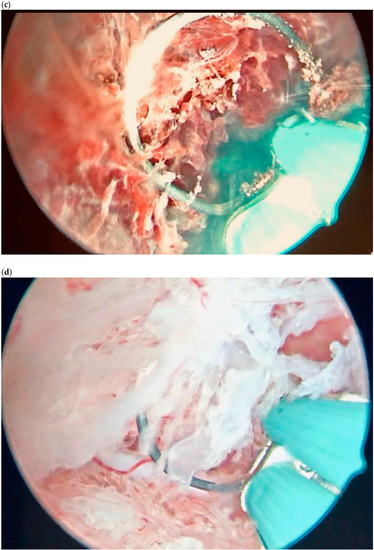

| Case 1 | Haemoperitoneum | unknow | 2495 | GS 30 mm (maximum diameter); on the right ovary | Surgical treatment (LPS) | Complete resolution |

| Case 2 | Haemoperitoneum | unknown | 2185 | GS 30 × 20 mm on the right ovary | Surgical treatment (LPS) | Complete resolution |

| Case 1 | Acute abdomen | 6 + 3 | N/A | GS 20 mm at the right wall of the peritoneum | Surgical treatment (LPS) + MTX IM 50 mg/m2 of body surface | Complete resolution |

| Case 2 | Haemoperitoneum | 7 + 2 | 53,716 | GS 30 mm located in the patch of the Douglas | Surgical treatment (LPS) | Complete resolution |